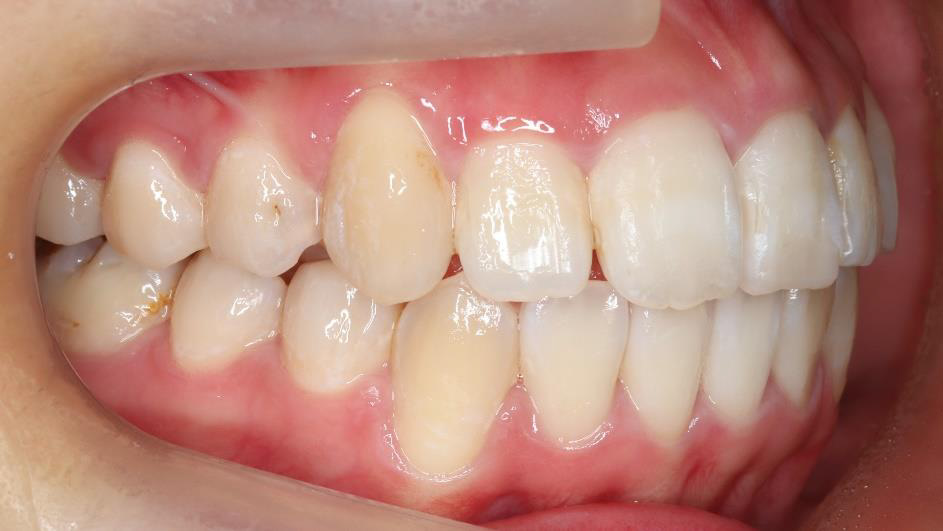

治療前

治療終了前

乱ぐい歯、でこぼこがとても酷い状態になります。歯が前後的に重なってしまっている、八重歯になっているなどがこのジャンルに入ります。

顎の大きさと歯の大きさのギャップが大きく、時には歯を抜かないと矯正治療ができない場合もあります。当院では治療期間が長くなるが抜かない治療方針など、一つの治療プランだけでなく、さまざまな可能性の治療方針を説明させて頂くよう心掛けております。こういった考え方はインフォームド・チョイスと言われ近年大切にされている考え方と言われております。